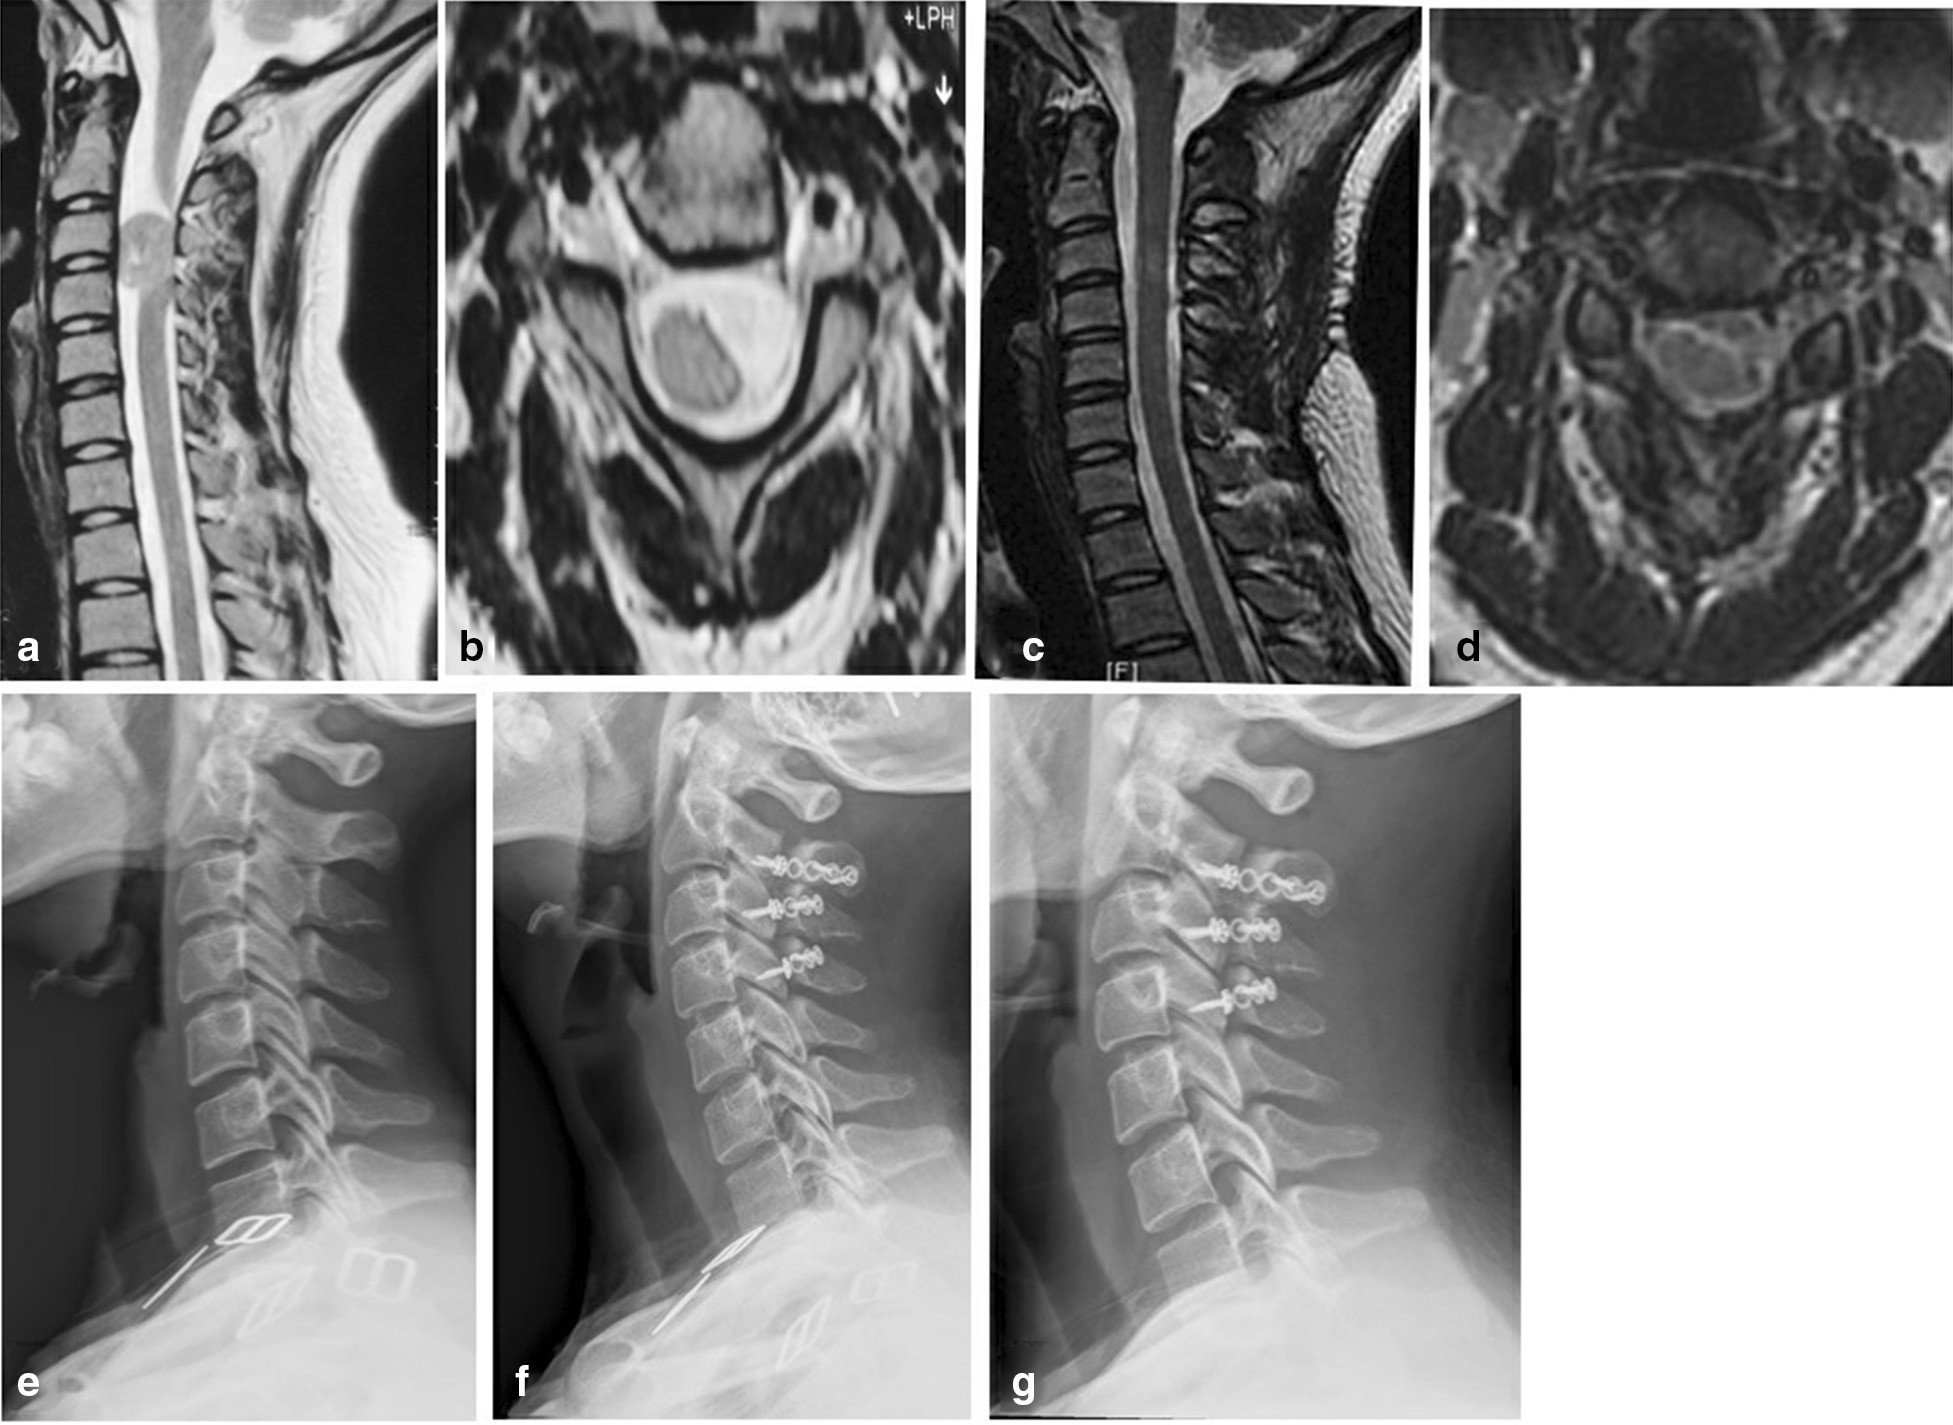

From: Application of open-door laminoplasty with ARCH plate fixation in cervical intraspinal tumors

Case 3. The schwannoma at the C3-4 level. a, b Prior to surgery, MRI identified that the C3-4 spinal space was occupied by the tumor. c, d At 12 months after the surgery, no intraspinal scar adhesions or restenosis were identified by MRI. e Prior to surgery, cervical X-ray examination was performed under the upright conditions. f, g At 12 months and 24 months after the surgery, X-ray examination indicated no fixation transposition or fracture, cervical instability or kyphosis